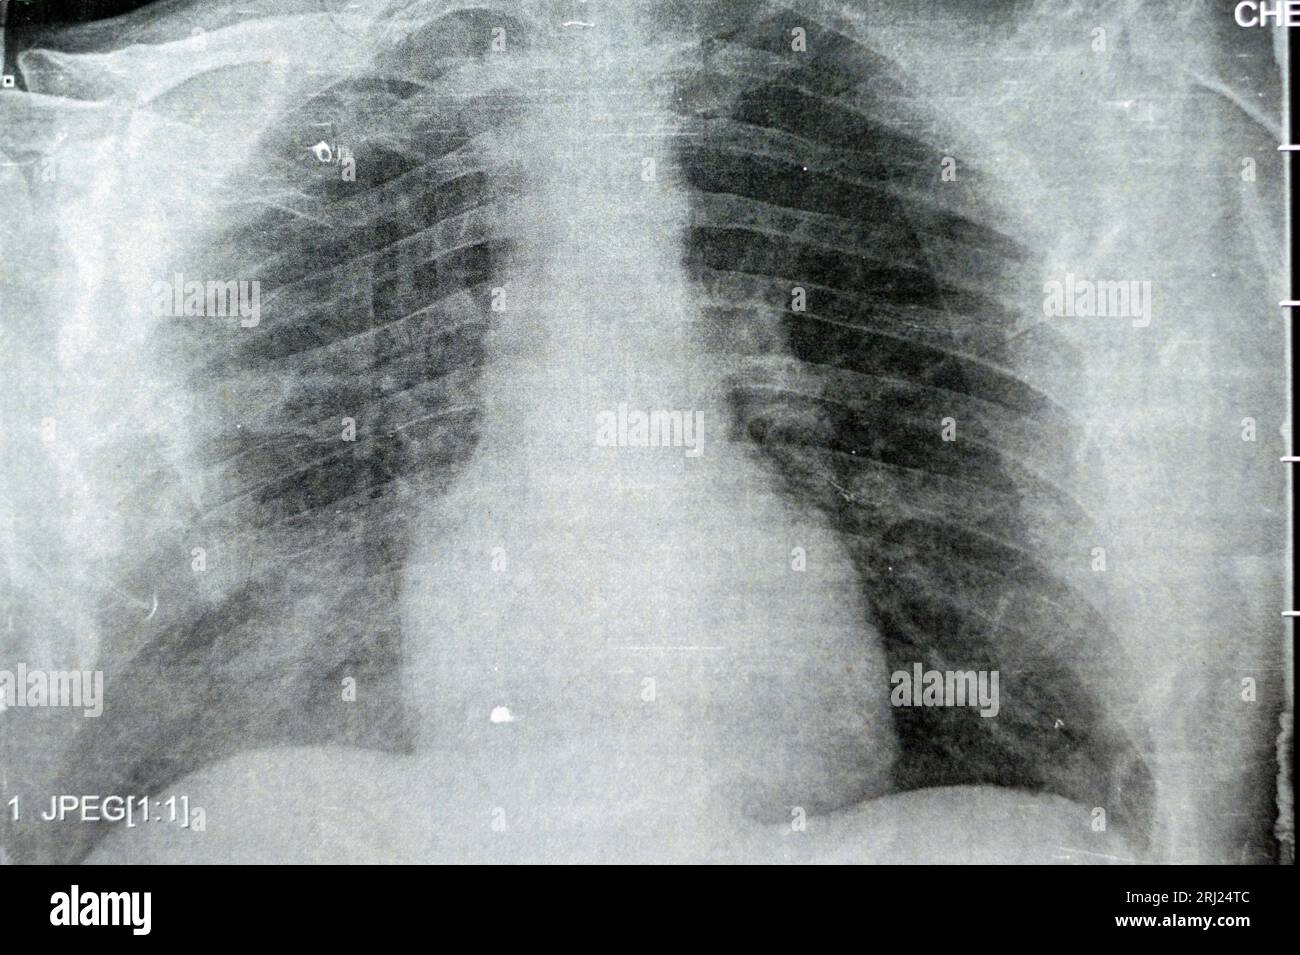

Chest Radiograph Pneumonia

Can A Chest X Ray Detect Pneumonia . your baby or young child has pneumonia; In hospital you'll usually be given fluids and antibiotics to treat the. If you are in hospital a chest x. doctors usually diagnose pneumonia by asking about your symptoms and examining your chest. It aims to improve accurate. This helps your doctor diagnose pneumonia and determine the extent and location of the infection.